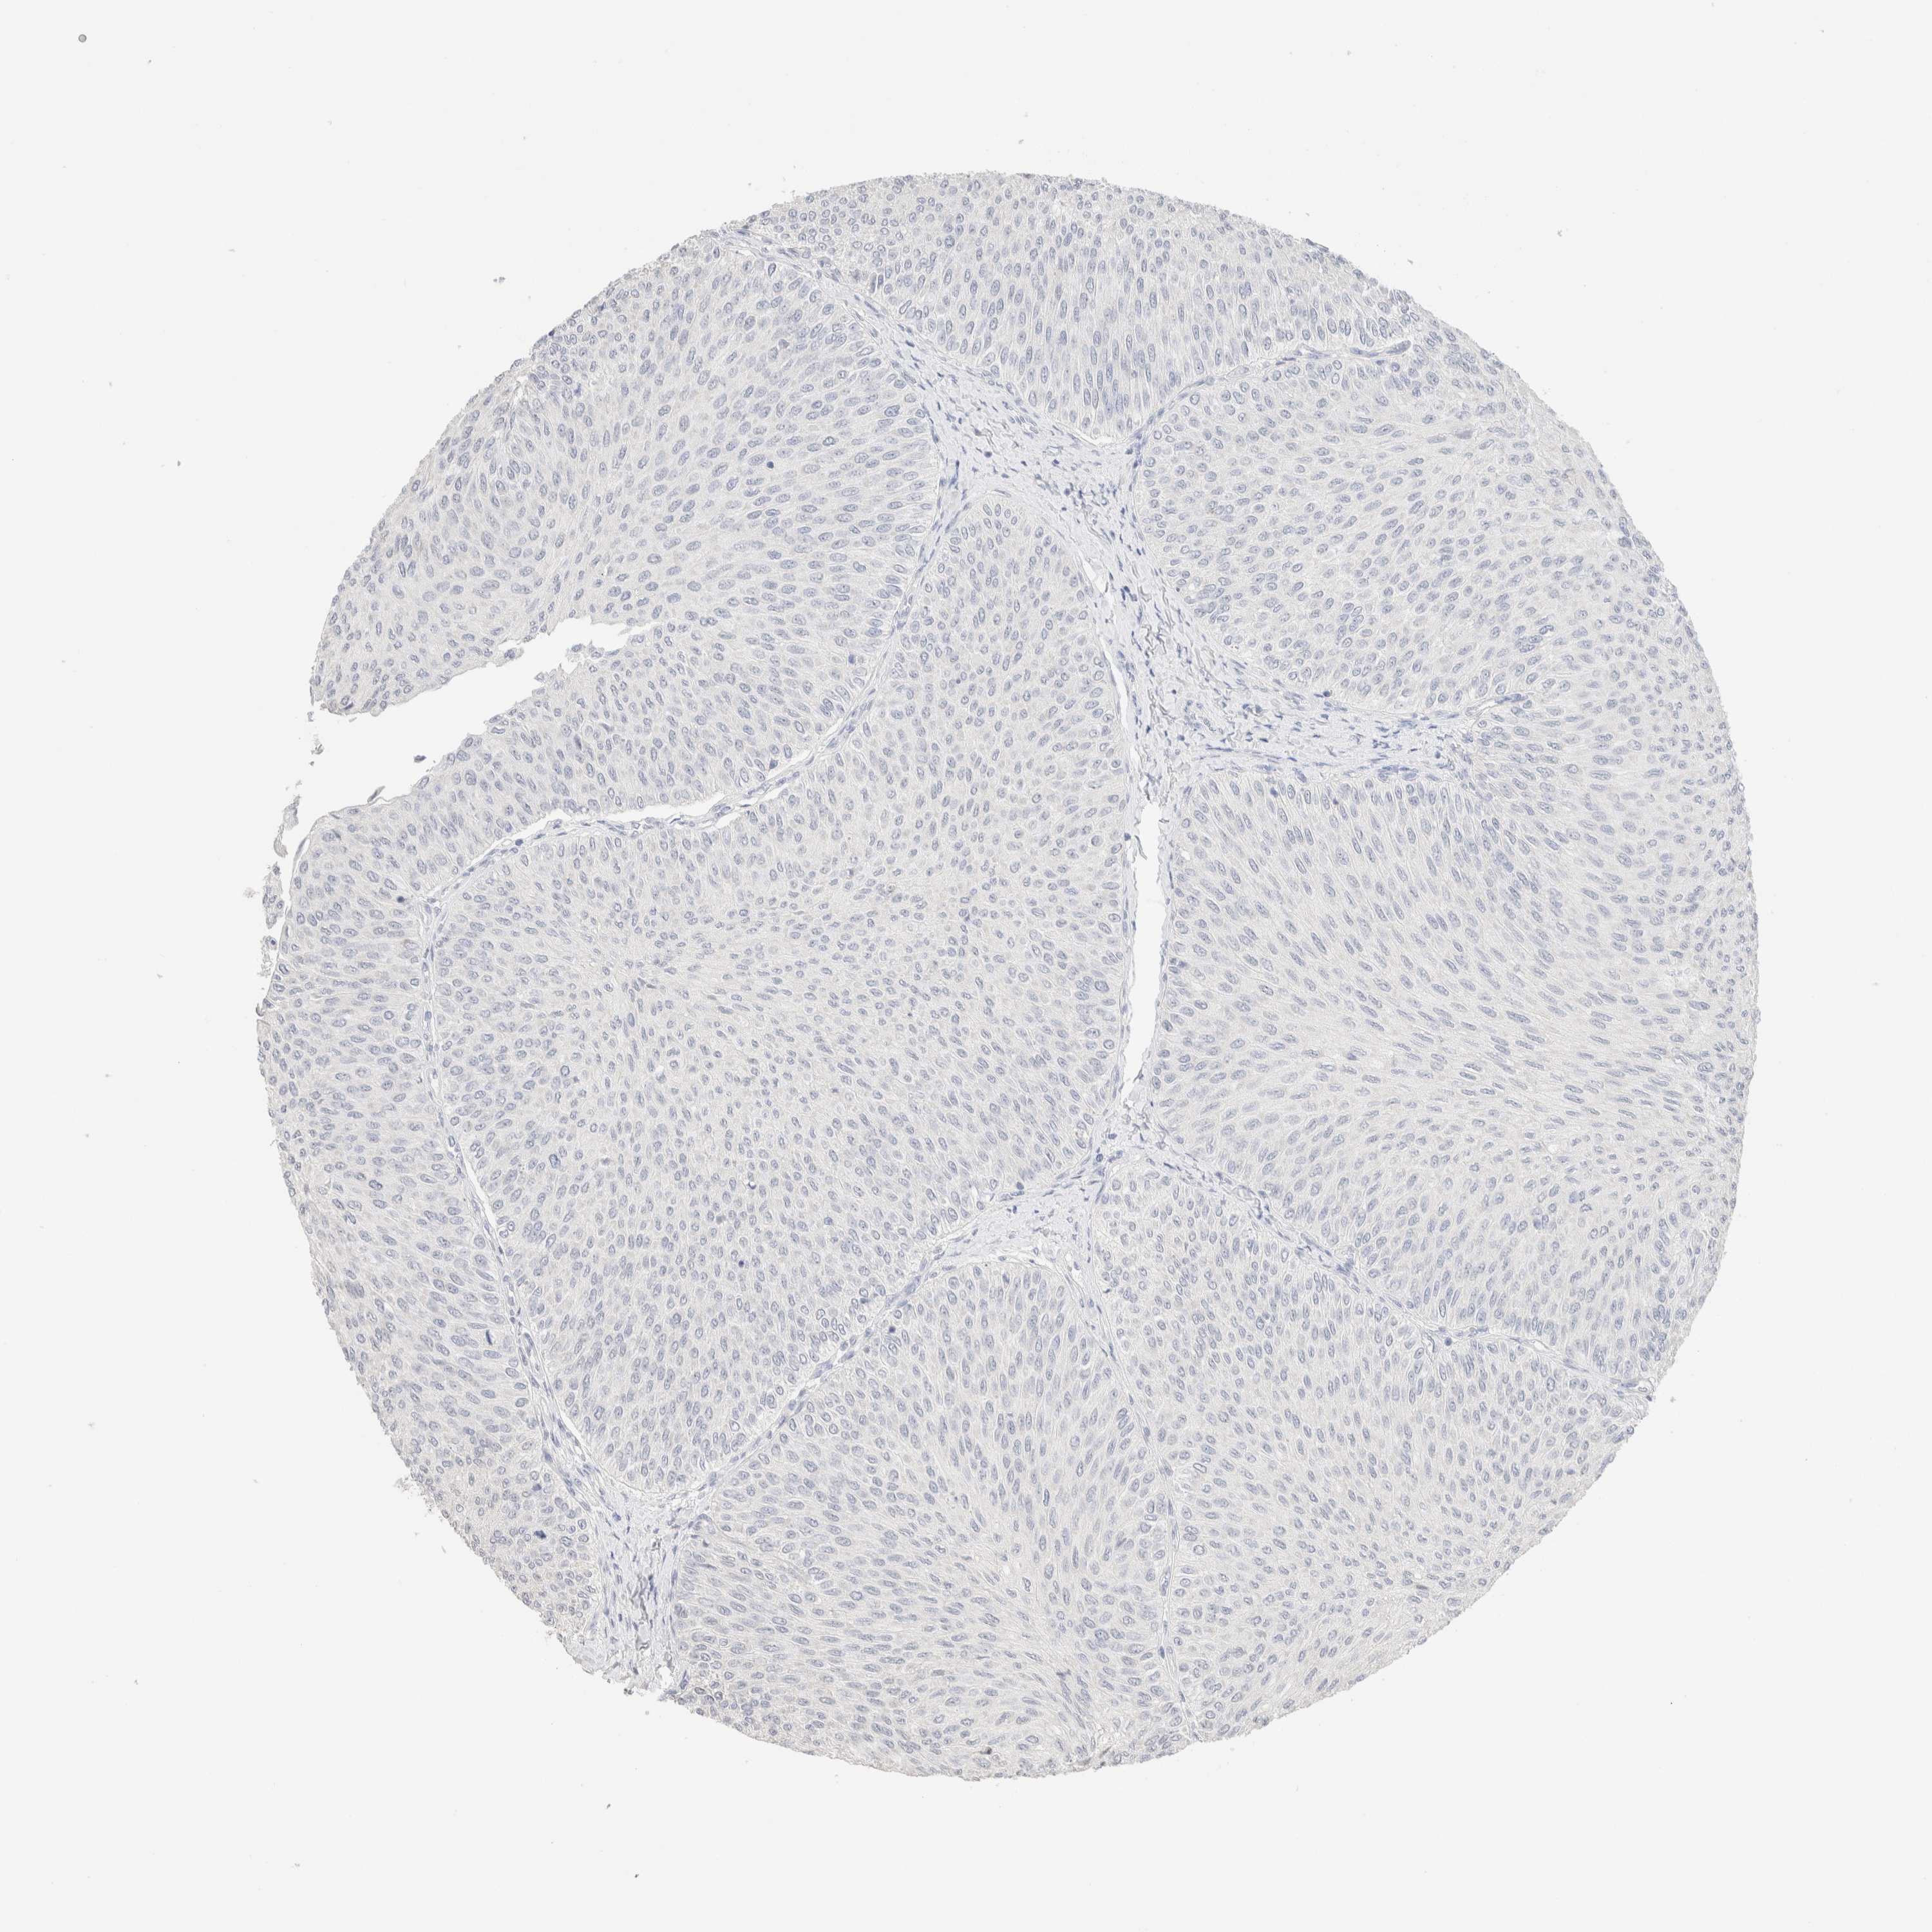

UROTHELIAL CANCER - Protein expressioni

A mouse-over function shows sample information and annotation data. Click on an image to view it in a full screen mode. Samples can be filtered based on level of antibody staining by selecting one or several of the following categories: high, medium, low and not detected. The assay and annotation is described here.

Note that samples used for immunohistochemistry by the Human Protein Atlas do not correspond to samples in the TCGA dataset.

Antibody stainingi

Antibody staining in the annotated cell types in the current human tissue is reported as not detected, low, medium, or high, based on conventional immunohistochemistry profiling in selected tissues. This score is based on the combination of the staining intensity and fraction of stained cells.

Each image is clickable and will lead to virtual microscopy that enables deeper exploration of all samples and also displays staining intensity scores, fraction scores and subcellular localization as well as patient and tissue information for each sample.

Antibody HPA022856

Antibody HPA023489

Urothelial carcinoma, Low grade

Urothelial carcinoma, High grade